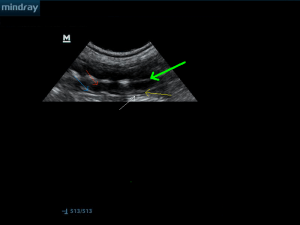

φυσιολογική διαστρωμάτωση λεπτού εντέρου, πράσινο βέλος αυλός του εντέρου( άσπρος λόγω ανάμειξης υγρού και αέρα), κόκκινο βέλος βλεννογόνος ( μαύρο), μπλέ βέλος υποβλεννογόνιος(άσπρο), κίτρινο βέλος μυικός χιτώνας (μαύρο), άσπρο βέλος ορογόνος (άσπρο)

κίτρινο βέλος ελέυθερο υγρό στη περιτοναική κοιλότητα, μπλέ βέλος κύστη του νεφρικού παρεχγχύματος, ροζ βέλη ακουστική ενίσχυση ( επιβεβαίωση πως πρόκειται για κύστη και όχι για κάποια υποηχογενή μάζα).